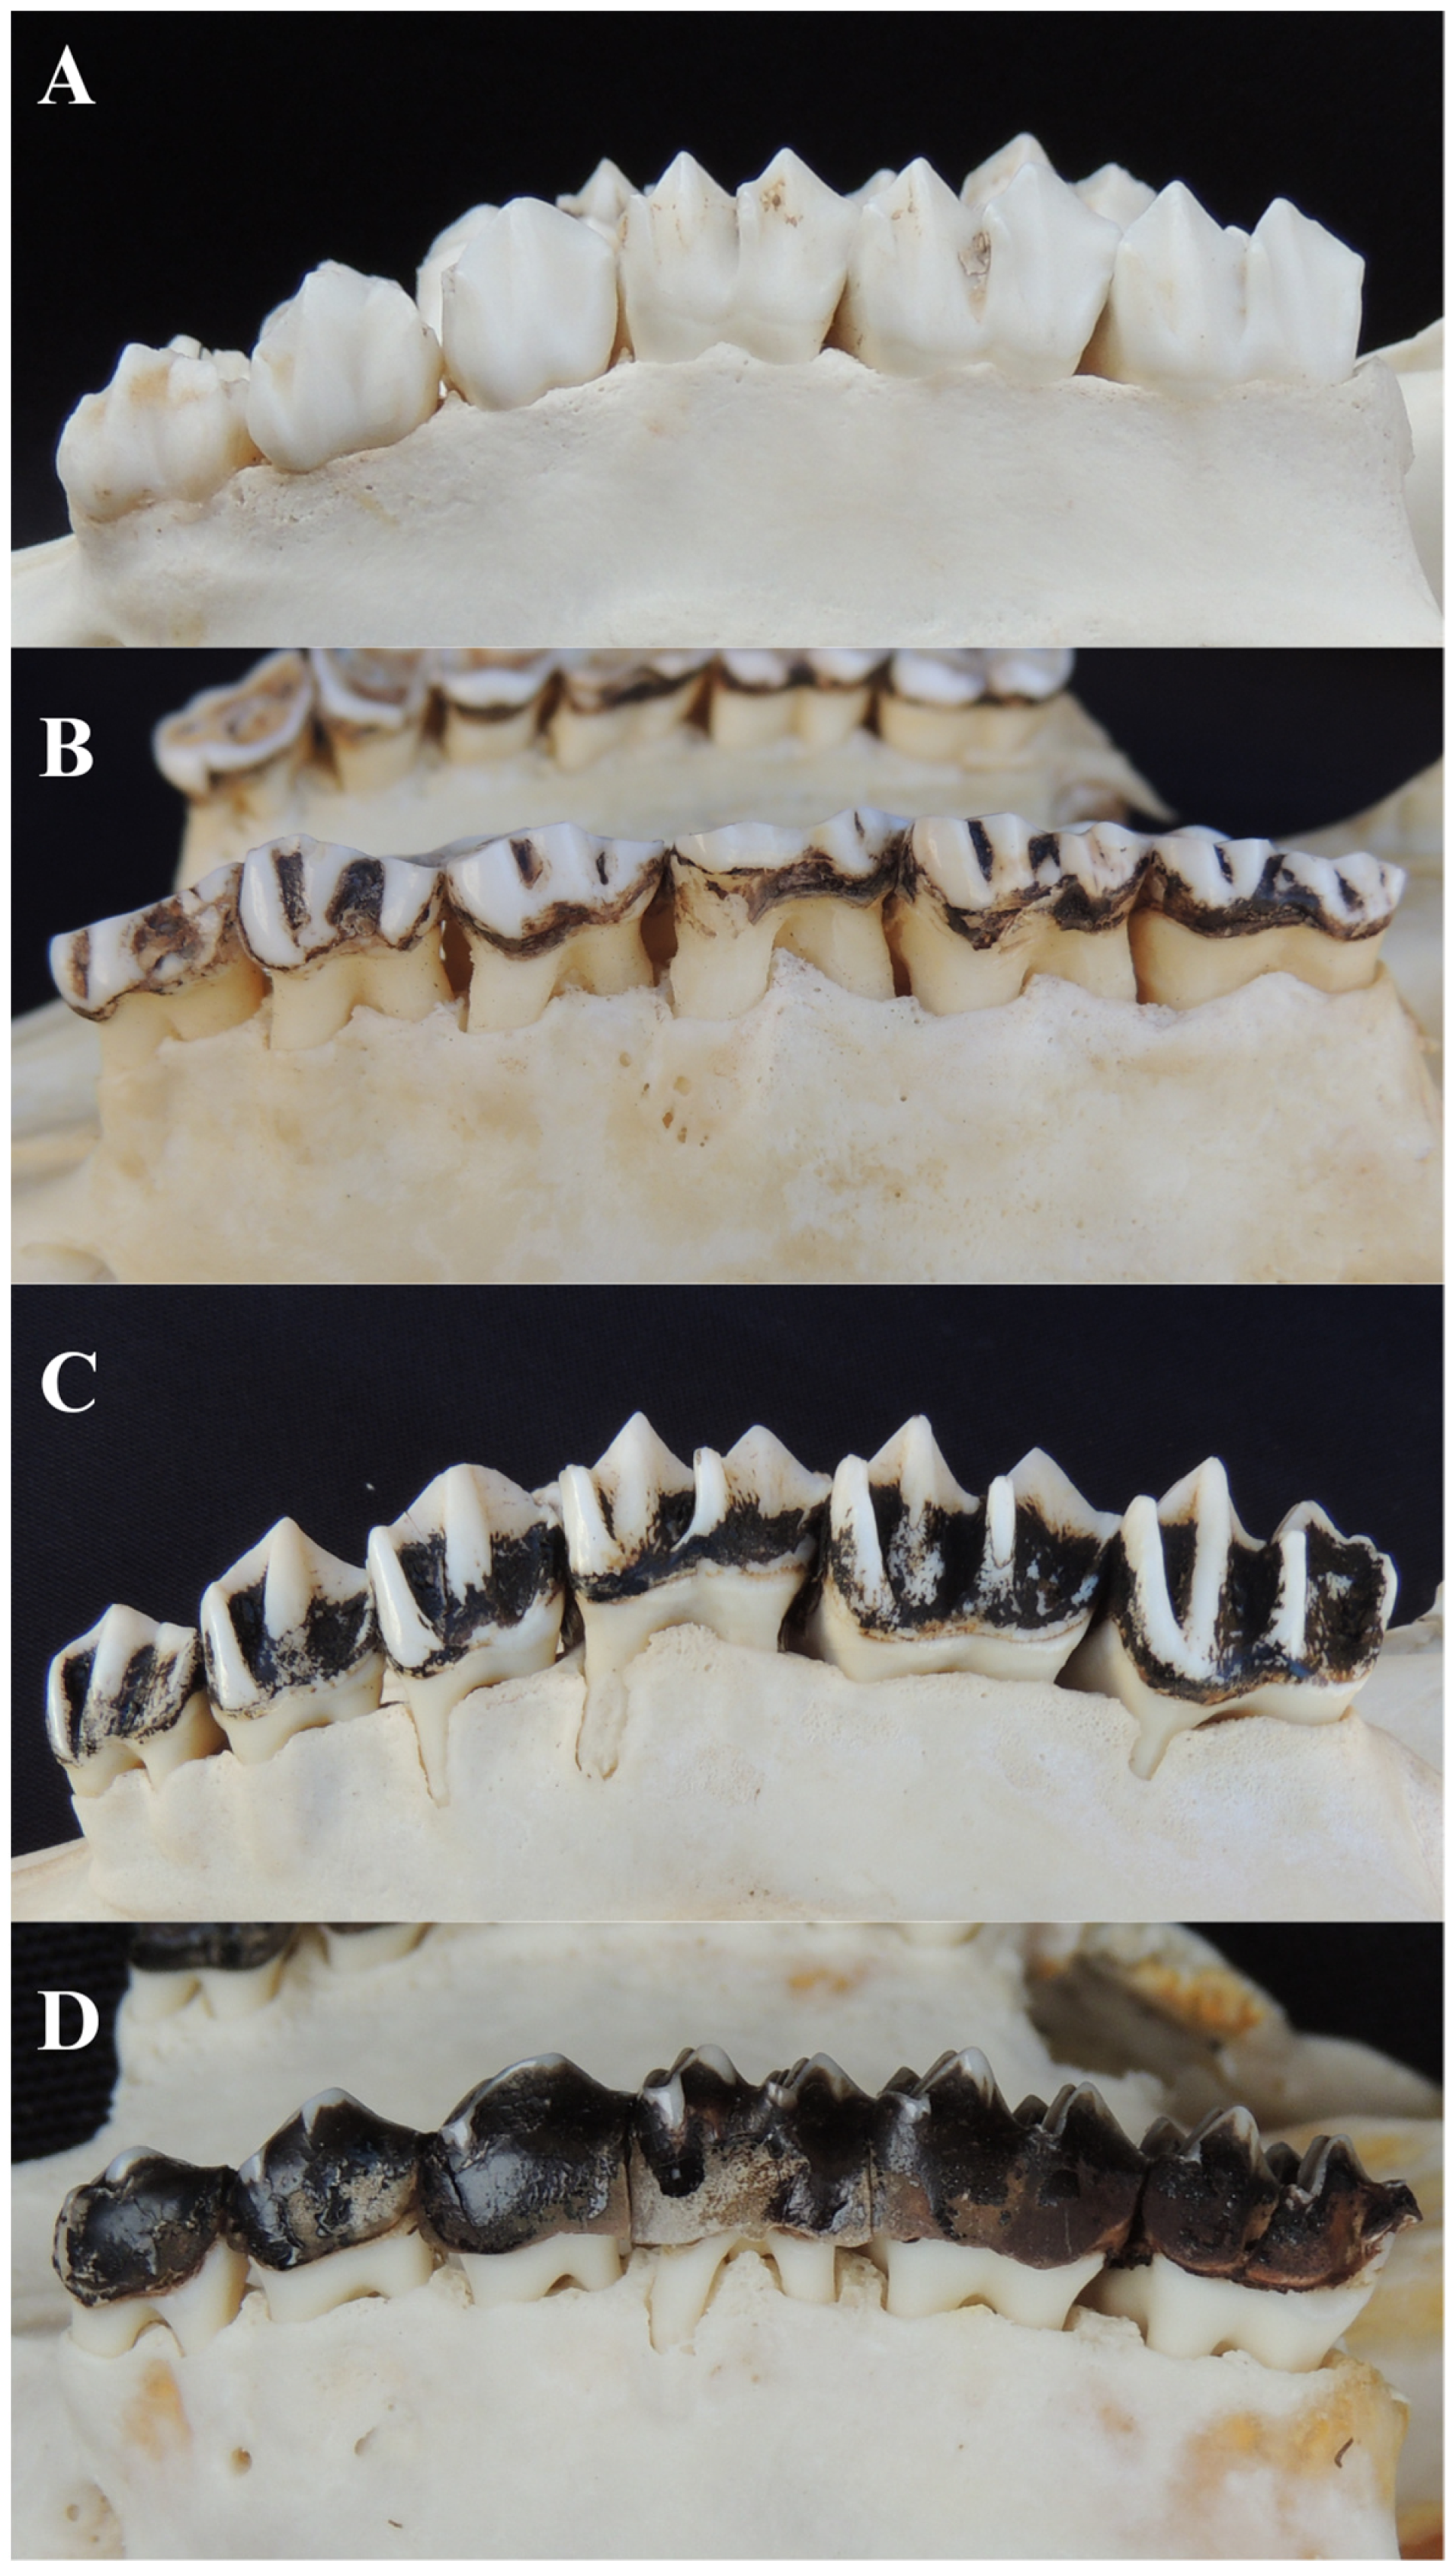

3.5.2. Tooth Wear and Dentine Exposure

3.5.3. Tooth Loss

3.5.4. Non-Functional Teeth

3.5.5. Tooth Fracture

3.5.6. Furcation Exposure

3.5.1. Dental Calculus